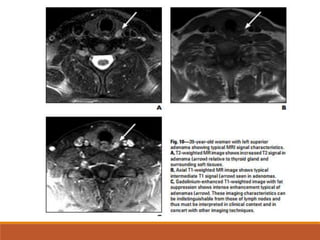

MRI

MRI is used in patients with persistent or recurrent

hyperparathyroidism, in whom it has been shown to be

effective in locating remaining abnormal parathyroid tissue.

The T1 and T2 characteristics of abnormal parathyroid

tissue are variable.

The most common tissue characteristics are intermediate-

to low-intensity T1 signal and high-intensity T2 signal.

false-negative studies are most commonly associated with

adenomas that are isointense on T1 and T2 sequences; the

addition of contrast-enhanced images can increase

sensitivity for these cases